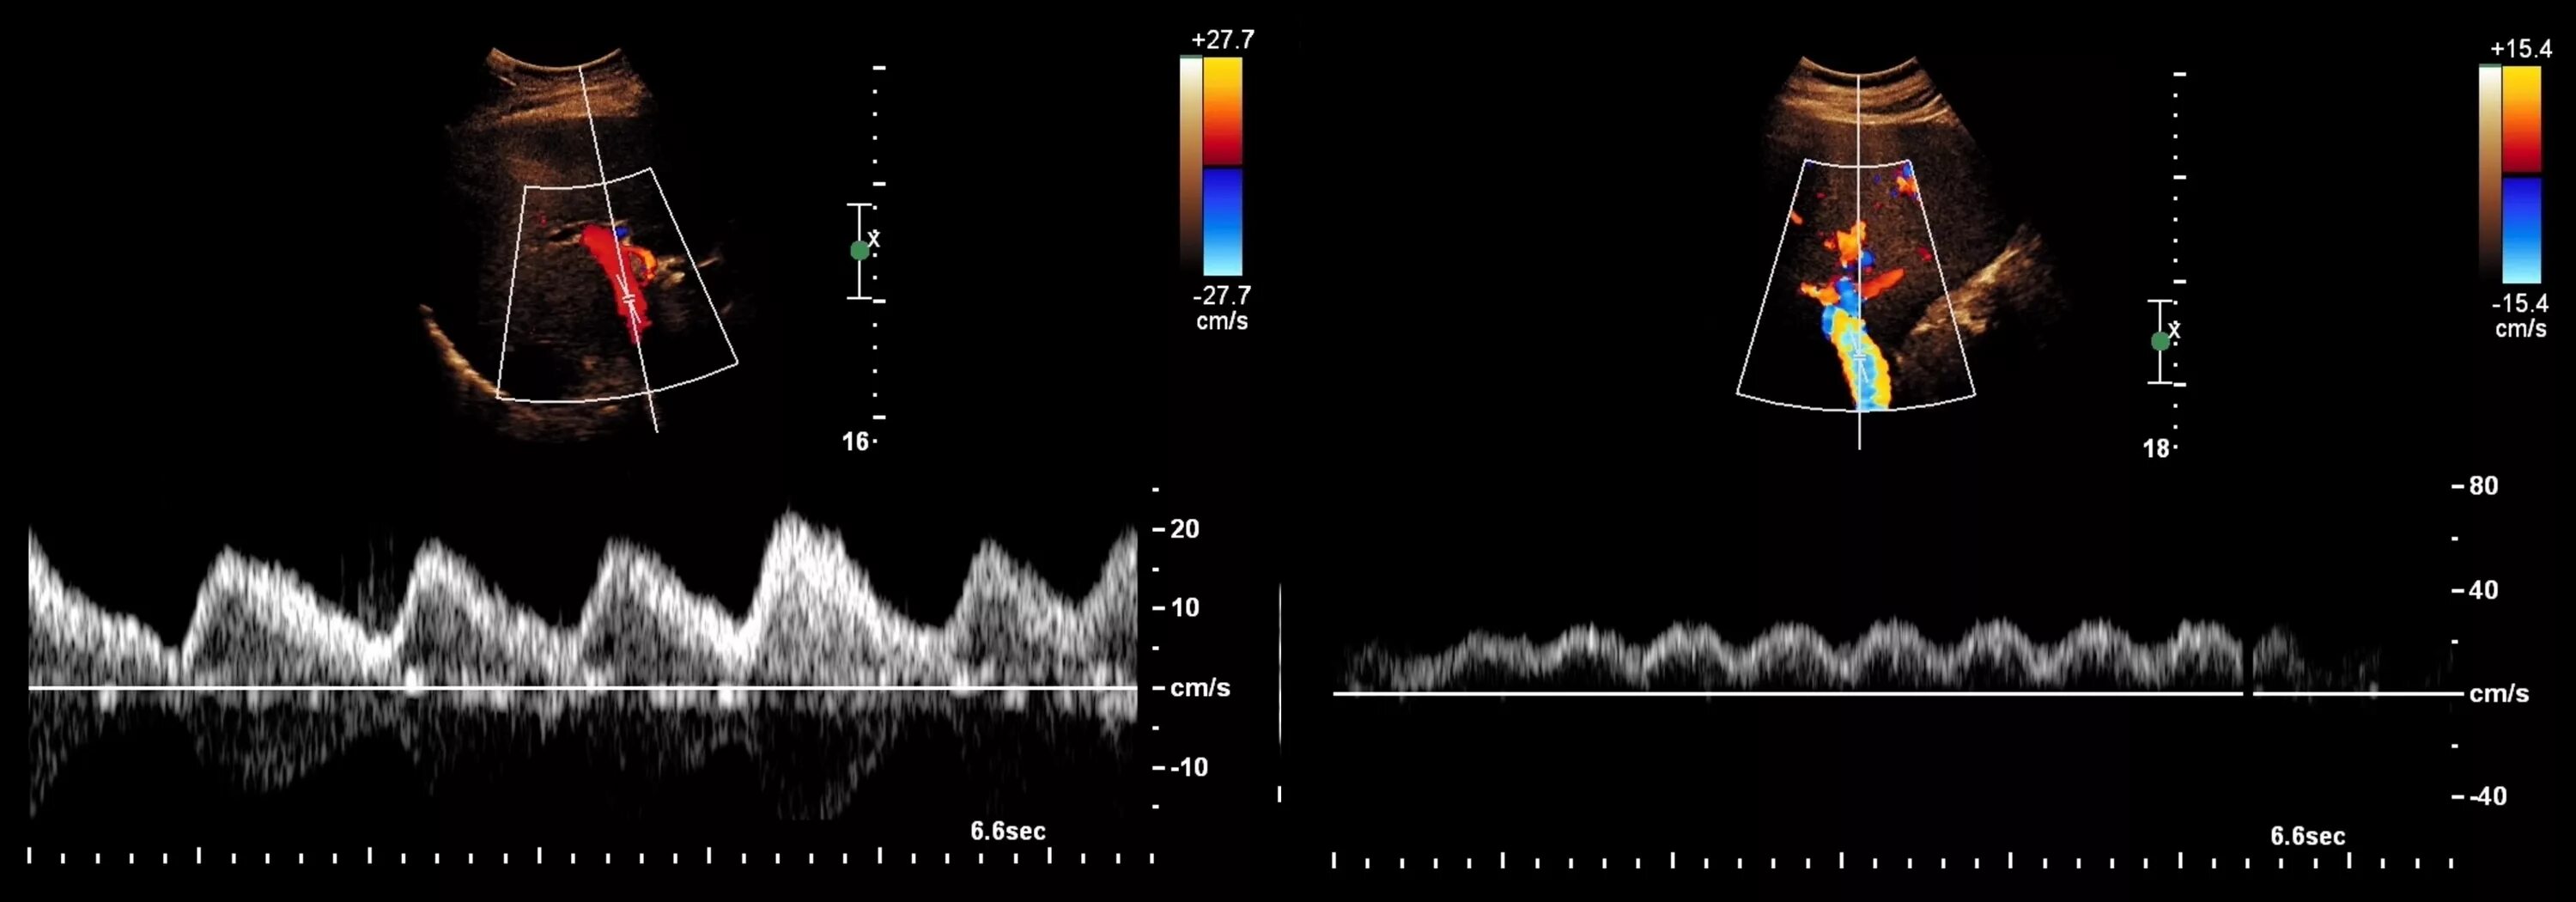

Тип кровотока 1 типа